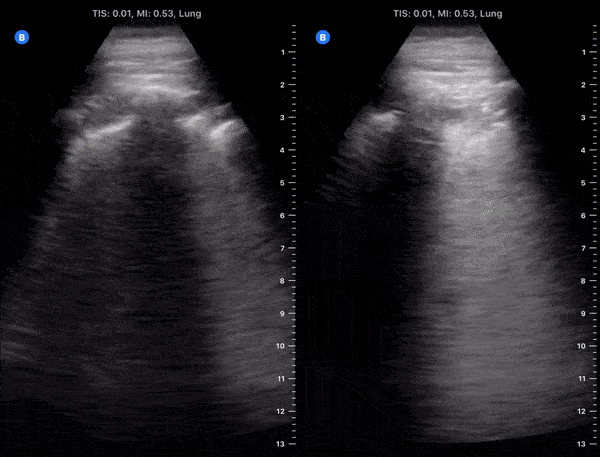

Pulmonary - Hospitalized COVID-19+ Patient on Day 9 of Symptoms [2/2]

These clips are taken from a patient admitted with COVID-19 pneumonia. The patient was on day 9 of symptoms. His cough had improved and fever resolved however he had hypoxia requiring supplemental oxygen. Lung ultrasound of left lower and left upper lobes demonstrating thickened irregular pleura, diffuse b lines (confluent) with subpleural consolidations. Image courtesy of Fritz Fuller (@POCUS_Society)